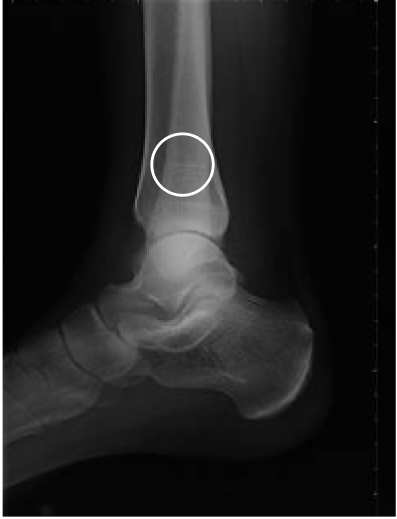

Tibial fracture

age 57